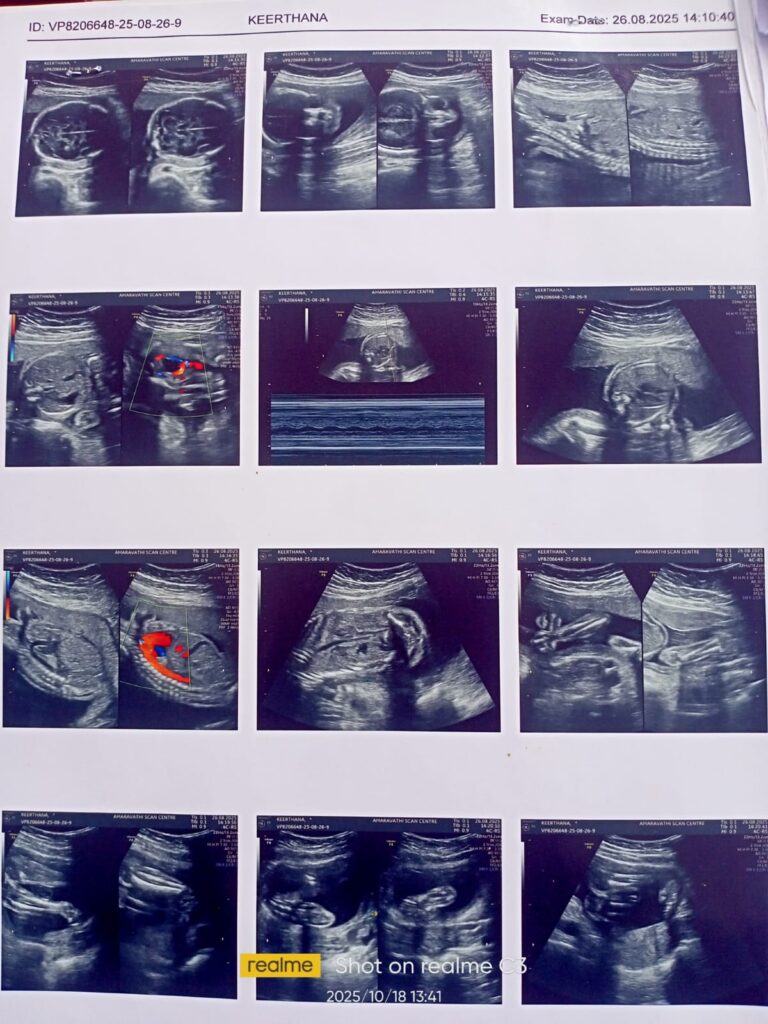

When the baby was 6 months old, doctors informed the mother that the baby had a kidney problem. Even the doctors could not give a guarantee. But iPulse gave strength and hope. Within 2 months, iPulse helped make the baby healthy. Now the baby is in good health and looks very beautiful, as shared by the parents.